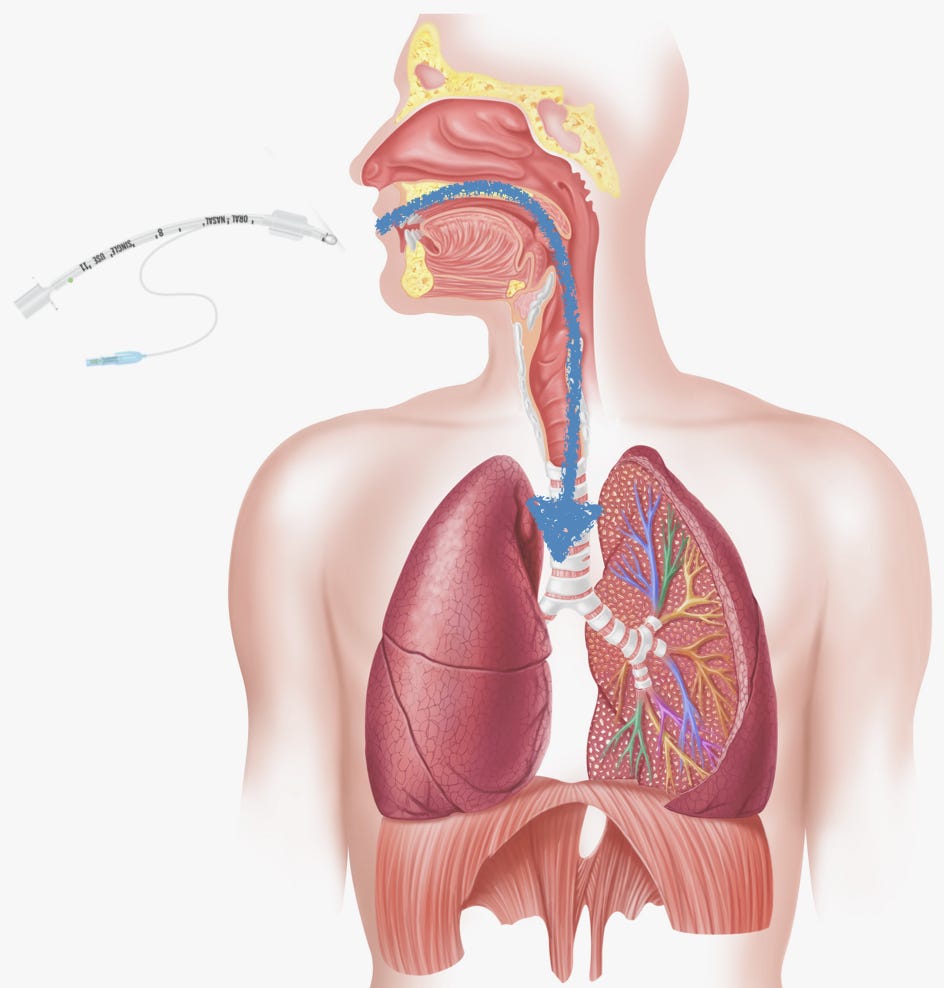

The idea is simple enough: Get the small plastic tube into the mouth, past the uvula (that bulbous thing that hangs down at the back of your mouth), between the vocal cords, and into the trachea. The tip of the tube should end up a couple of inches above where the trachea (a.k.a. the windpipe) splits in two, one for each lung. Once achieved, you connect the top of the tube to a breathing machine (a ventilator) that supplies oxygen.

Making live video feedback standard, it was hoped, would negate the need to perfectly line everything up to enable a sightline from a patient’s open mouth all the way to their vocal cords. Here’s a diagram of the setup needed for intubation without video assistance.